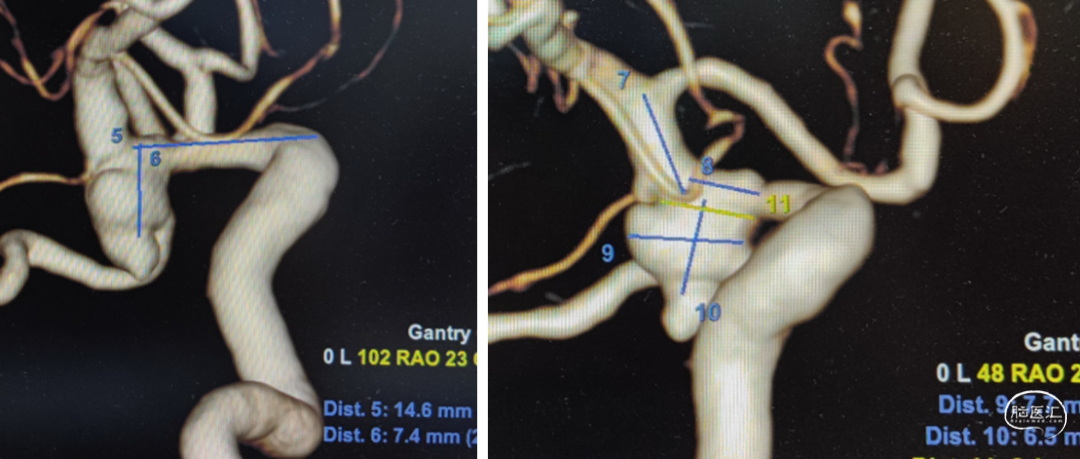

头颅CTA

支架选择

LEO3.5x25 Atlas 3.0x15

Axium3d620;axium3d15

管2:target3d24